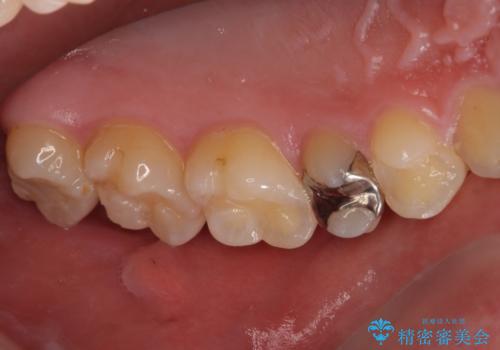

- 「左右どちらとも、どこかが痛む」とご来院された患者様です。

他院で虫歯治療を複数行っており、原因となりうる歯がいくつかありました。まずレントゲン上最もあやしい右上から治療開始しました。右上の歯は1本割れていたため、部分矯正で引っ張り出しました。

右上もう1本と左上は虫歯治療(セラミックインレー、セラミッククラウン)を行いました。